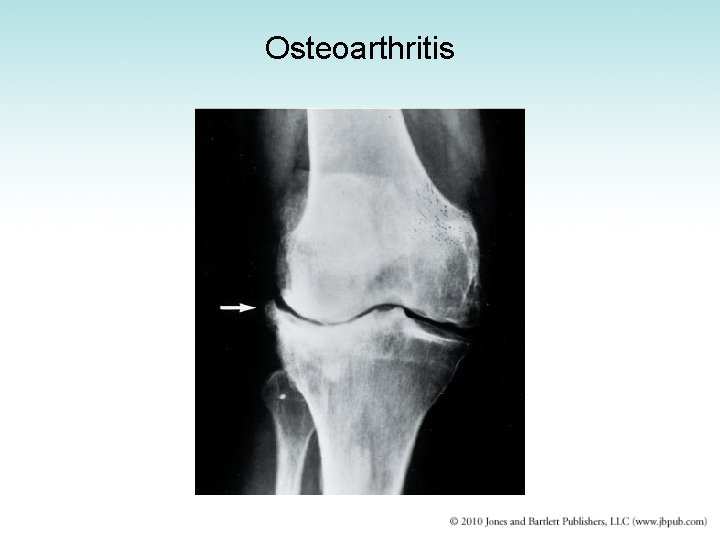

Osteoarthritis • Not a systemic disease • “Wear and tear” degeneration of one or more weight-bearing joints • Causes degeneration of articular cartilage • Seen in older adults, considered a manifestation of normal aging process • Treatment: drugs; joint replacement if severe

Advanced osteoarthritis

Osteoarthritis